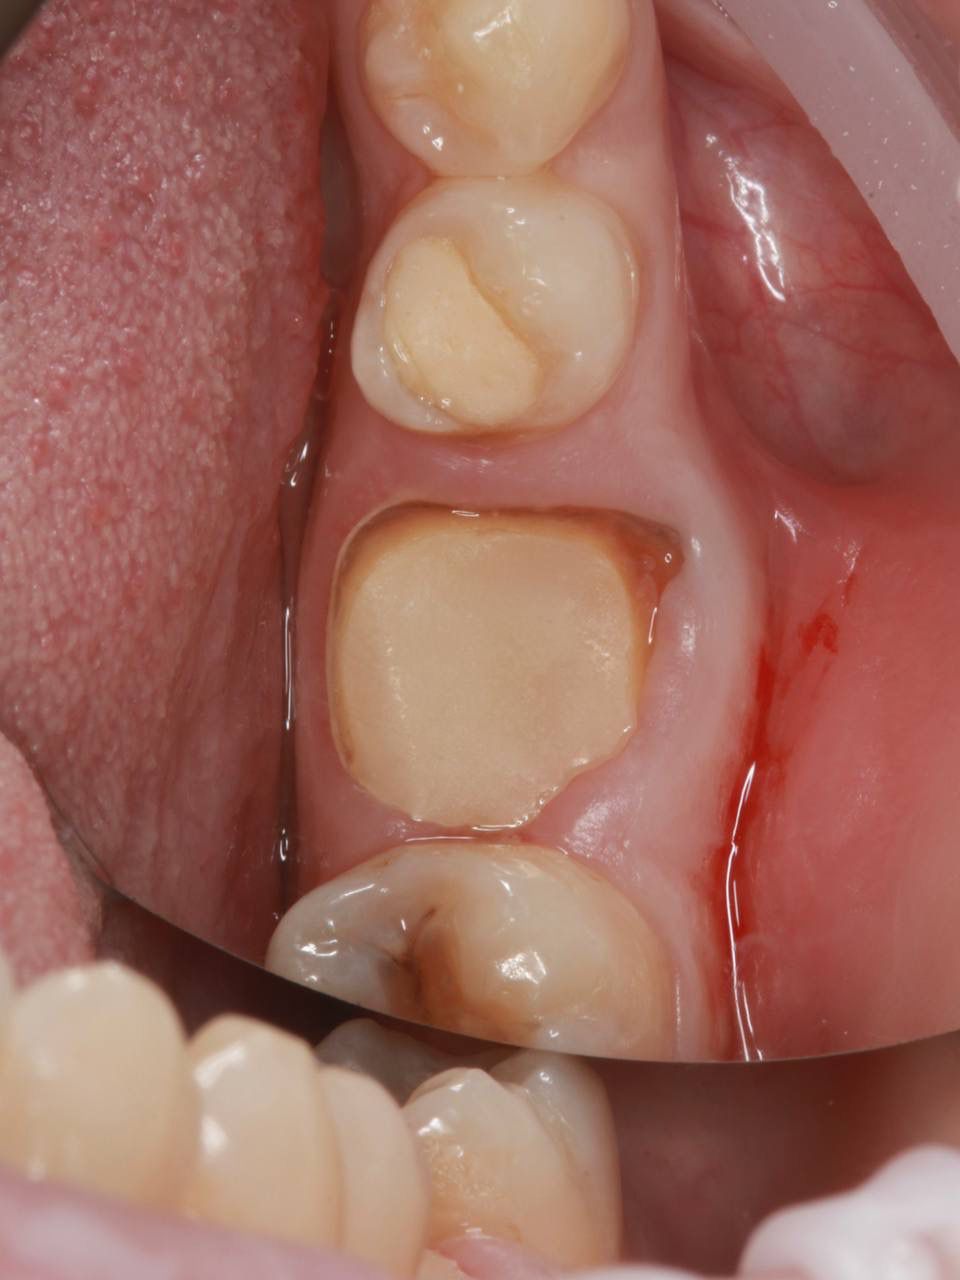

Одномоментная имплантация системой Osstem(Ю. Корея), подшит трансплантат с бугра(для увеличения объема мягких тканей), установлен формирователь десны. Через 3 месяца установлена коронка из диоксида циркония на винтовой фиксации